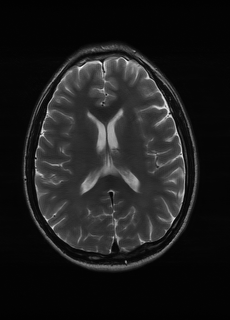

As we observe from the right image in Fig. 2, our BRM, both from MIMO and SISO settings, predicts the performance of dedicated models with a high correlation. We further choose the best three , and perform the last stage of fine-tuning accordingly to (6). A visual evaluation on real data is shown in Fig. 3. For simulated data, please refer to the Supplemental Material section.

Base on the best performing , we perceive that among , , and FLAIR, the results are best when is sampled the most. We suggest that this makes intuitive sense as images provide the best contrast out of the three sequences, which can compensate for the details lost in other images. The same observation can be made on the simulated data, where both and FLAIR show good contrast. When the time setting is changed to non-uniformity, we can see that our search for the best sampling strategy reflects the change. is sampled more as a result of faster acquisition time, while is still sufficiently sampled.

| Sequence | LR | SISO | MIMO | MIMO tuned | GT |

|---|---|---|---|---|---|

(a) 34.38/0.9371

(a) 34.38/0.9371

|

(b) 42.42/0.9883

(b) 42.42/0.9883

|

(c) 44.60/0.9920

(c) 44.60/0.9920

|

(d) 45.50/0.9940

(d) 45.50/0.9940

|

(e) PSNR/SSIM

(e) PSNR/SSIM

|

|

(f) 29.74/0.8903

(f) 29.74/0.8903

|

(g) 36.25/0.9734

(g) 36.25/0.9734

|

(h) 36.42/0.9752

(h) 36.42/0.9752

|

(i) 37.70/0.9832

(i) 37.70/0.9832

|

(j) PSNR/SSIM

(j) PSNR/SSIM

|

|

(k) 39.89/0.9311

(k) 39.89/0.9311

|

(l) 43.94/0.9864

(l) 43.94/0.9864

|

(m) 44.74/0.9883

(m) 44.74/0.9883

|

(n) 45.49/0.9894

(n) 45.49/0.9894

|

(o) PSNR/SSIM

(o) PSNR/SSIM

|